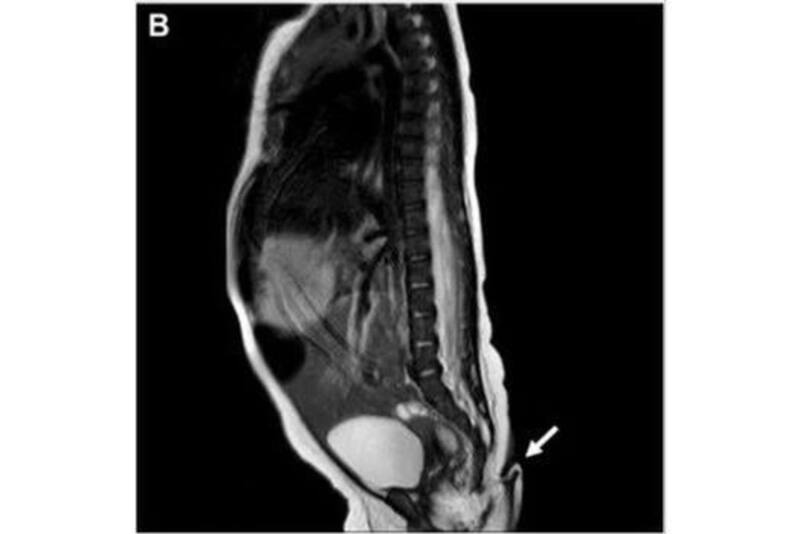

La extremidad adicional sólo fue visible fuera del vientre de su madre. Tenía una longitud de 5.7 centímetros, con entre 3 y 5 milímetros de diámetro y se encontraba en la hendidura interglútea. Se realizó una radiografía donde se descartó que la cola tuviera algún hueso o tipo de irregularidad.

Asimismo, se hizo una ecografía que confirmo la inexistencia de alguna malformación renal o de tracto urinario. Tras descartar que el bebé no tenía otro defecto congénito, la enviaron a casa para continuar con el tratamiento de forma ambulatoria.